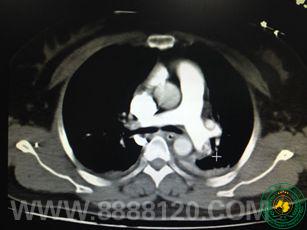

宜宾二医院重症医学科成功救治一例肺栓塞伴呼吸心跳骤停患者

宜宾二医院重症医学科成功救治一例肺栓塞伴呼吸心跳骤停患者6809